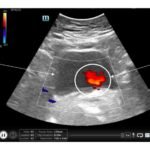

Point-of-care ultrasound is often used as first line imaging for the evaluation of flank pain in the emergency department and can potentially expedite diagnosis or decrease the use of abdominal CT scans, preventing unnecessary radiation exposure. This is a case report of a 77-year-old female who presented with acute flank pain. Point-of-care ultrasound revealed the absence of a ureteral jet on the right side, supporting the diagnosis of ureteral obstruction, which was confirmed on computed tomography. This case report aims to demonstrate the value of identification of ureteral jets when using point-of-care ultrasound to diagnose ureteral obstruction. Knowledge of more subtle and specific ultrasound findings such as this can help expedite more precise diagnoses.

Ureteral obstruction, ureteral jets, hydronephrosis, renal colic, renal calculi, point-of-care ultrasound, flank pain.